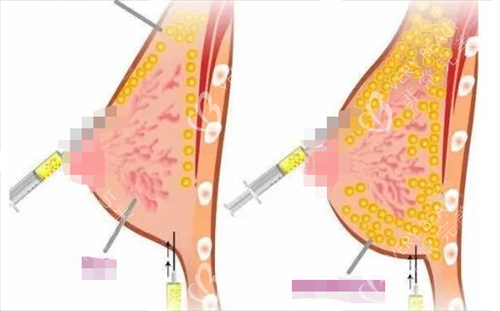

蜜瓜医院做胸擅长 “复合型丰胸”,很适合自身脂肪量足够,又想让胸型更饱满的小伙伴。比如会先抽取腰腹或大腿的脂肪,经过提纯后注射到胸部,再搭配小号假体,既能增加胸部体积,又能让手感更接近原生胸。医生还会看重胸型的对称性,术后左右胸大小误差能控制在很小范围,很多追求 “妈生感” 胸型的顾客都选这家。